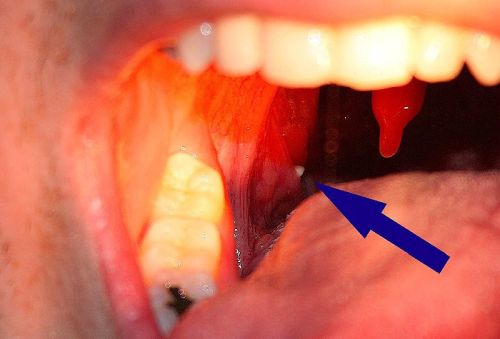

La presenza di materiale bianco sulle tonsille non sempre è indice di placche. Se non si ha febbre e il materiale bianco è visibile solo in alcuni punti delle tonsille allora è probabile che si tratti di tonsilloliti, altrimenti detti calcoli delle tonsille. I tonsilloliti sono composti da depositi di cibo, batteri e cellule morte che vanno a formarsi nelle cosiddette cripte tonsillari, cioè delle sacche presenti sulla superficie delle tonsille.

Le cripte tonsillari possono essere anche molto ampie e profonde a causa di forti tonsilliti con placche che contribuiscono ad ampliarle in modo permanente. All’interno delle cripte tonsillari dunque può sedimentarsi molto materiale che produrrà dei tonsilloliti di dimensioni anche molto grandi.

- Presenza di materiale solido di color bianco nelle cripte tonsillari, visibile a occhio nudo illuminando le tonsille con una torcia;